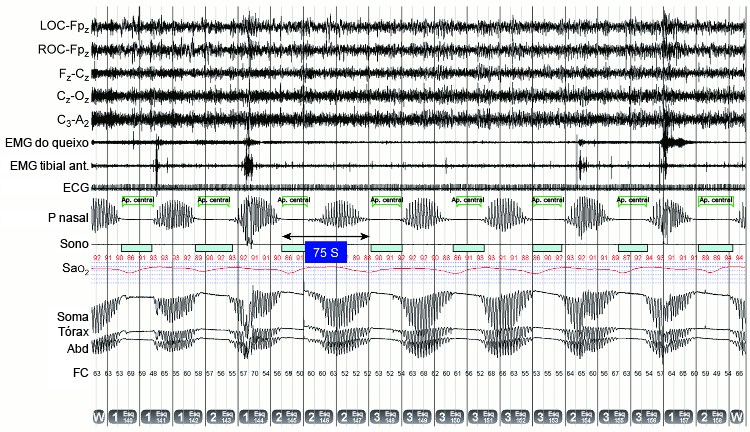

Respiração de Cheyne-Stokes: polissonografia demonstrando o característico aumento e diminuição da ventilação separada por apneias centrais (melhor observado no sinal do transdutor de pressão nasal [P nasal] e abdominal [Abd], torácico [Tórax] e na soma dos traços de impedância respiratória), resultando em dessaturações quase sinusoidais na saturação de oxiemoglobina. A duração do ciclo entre eventos é de 75 segundos; o eletrocardiograma (ECG) revela fibrilação atrial, ambos característicos de um paciente com insuficiência cardíaca avançada

Distúrbios respiratórios relacionados ao sono. In: Krahn L, Silber M, Morgenthaler T. Atlas of sleep medicine. Nova York. Informa Healthcare, 2011. Com permissão da Mayo Foundation for Medical Education and Research. All rights reserved